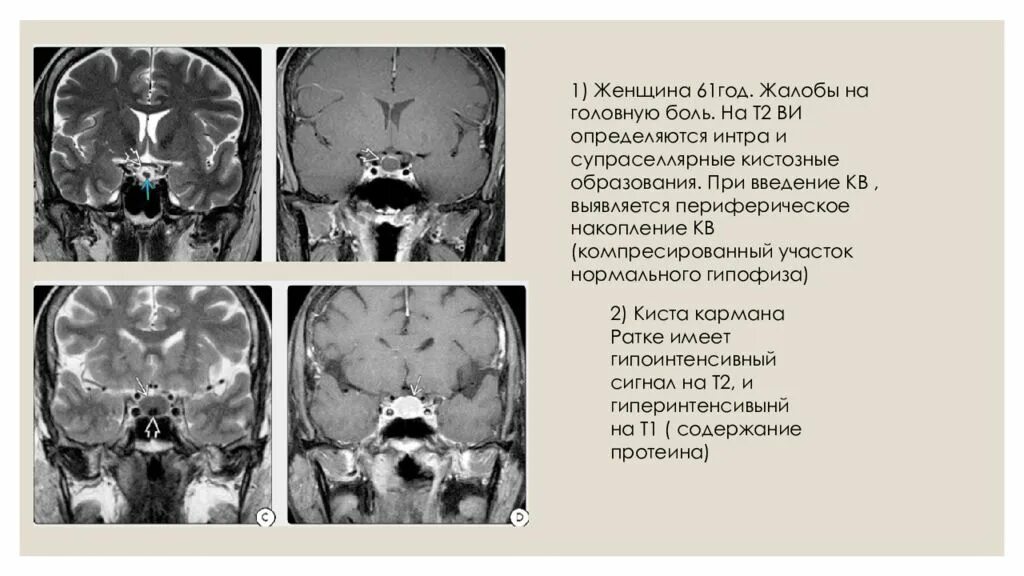

Гипофиз мрт норма